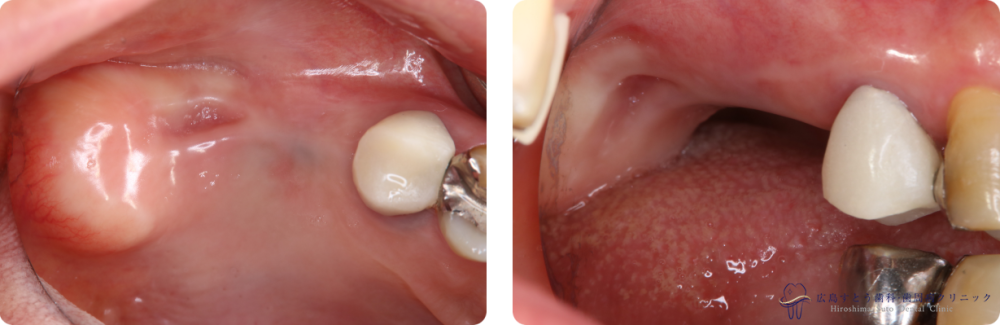

Case1

Before

初診時の状態

初診時の状態

After

メンテナンス開始時

メンテナンス開始時

術前

初診時の状態:矢印の歯は予後不良のため抜歯になりました

右上の抜歯後の状態:歯肉が陥凹してしまっています